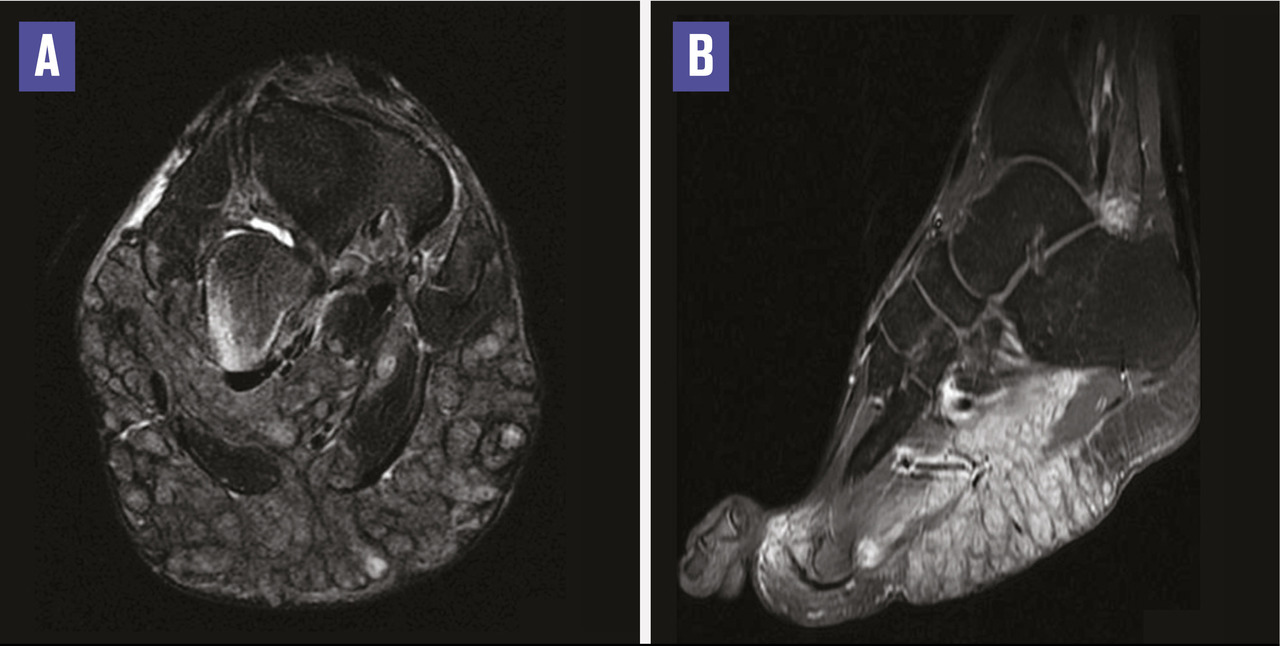

Ce jeune homme de 24 ans consultait pour une tuméfaction polyfistulisée de la plante du pied droit laissant sourdre des grains noirâtres millimétriques (fig. 1). À l’échographie, on notait des collections hypoéchogènes centrées par des images hyperéchogènes correspondant à des grains de mycétome. L’imagerie par résonance magnétique montrait un processus tissulaire de la plante, multiloculé, en hypersignal hétérogène T2 (fig. 2A), en hyposignal T1, se rehaussant fortement après injection du gadolinium avec des ponctuations restant en hyposignal (fig. 2A). La tomodensitométrie montrait une érosion du bord externe de l’os cuboïde. Devant cette tuméfaction d’évolution lente et la présence de grains visibles, le diagnostic de mycétome était évoqué. Une biopsie confirmait le diagnostic de mycétome fungique à Madurella mycetomatis. Le patient était traité par itraconazole (200 mg/j), sans succès. L’exérèse chirurgicale était décidée en réunion multidisciplinaire.